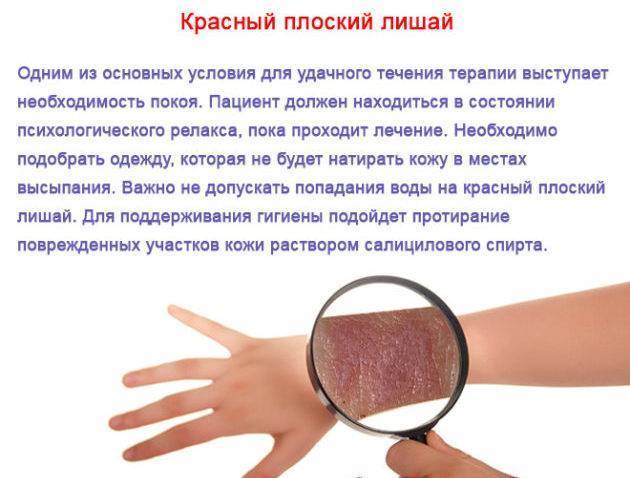

Фото Красного Плоского

Фото Красного Плоского 103 фото